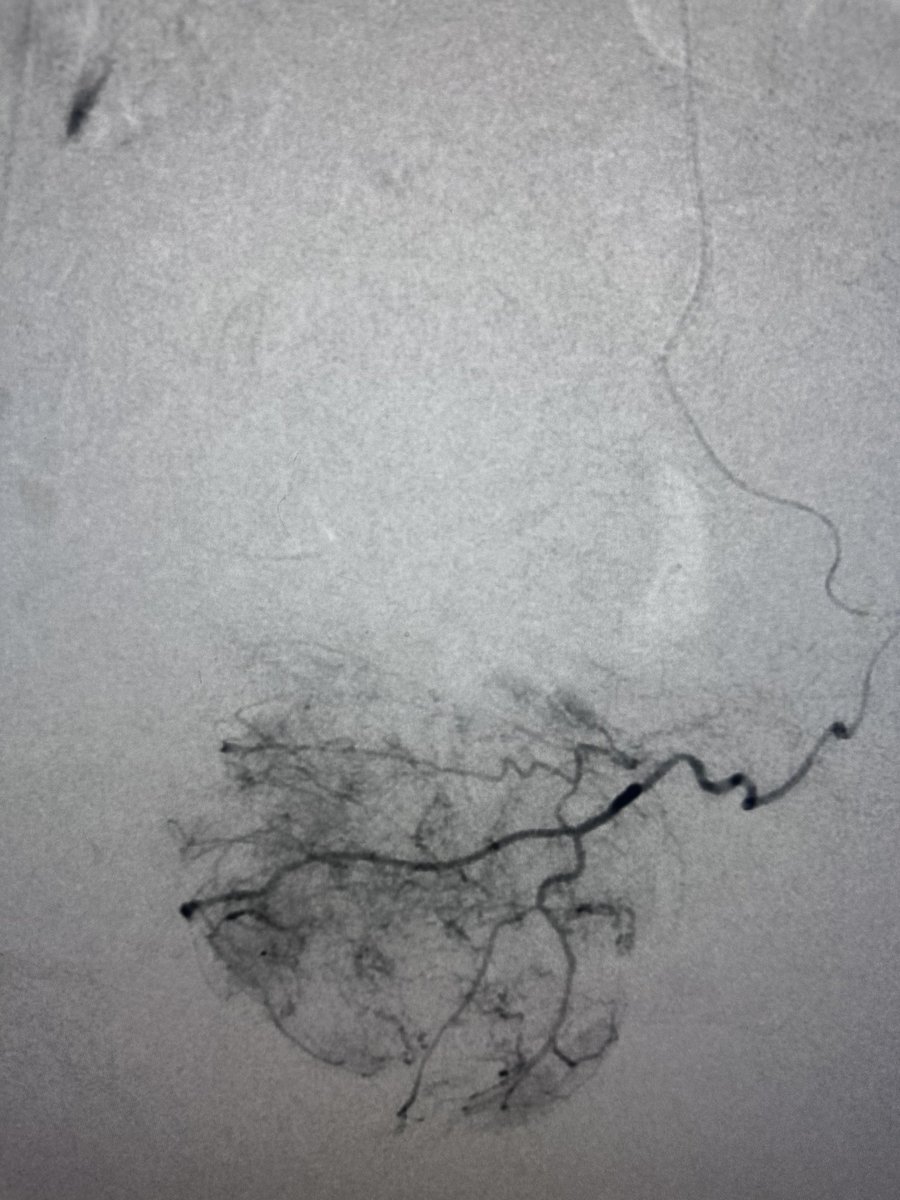

Prostatic artery embolization (PAE) is a game-changer for men with benign prostatic hyperplasia (BPH)! A minimally invasive procedure that reduces prostate size, improves urinary symptoms, can promote a faster recovery compared to traditional surgery. #BPH #MenHealth #PAE #ProstateHealth #MedicalInnovation

Prostatic artery embolization is the most cost-effective minimally invasive therapy for patients with benign prostatic hyperplasia. @UCSF_IR @UCSFimaging @XiaoWuMD @mheller14 bit.ly/41iXXeB